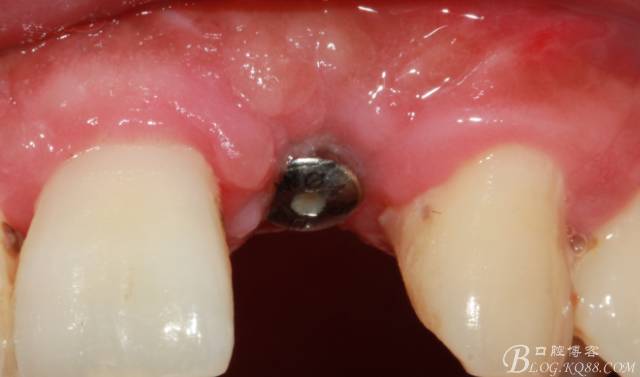

4個(gè)月后,唇側(cè)豐滿度尚可,與鄰牙之間齦乳頭完整。

保留齦乳頭翻小瓣。